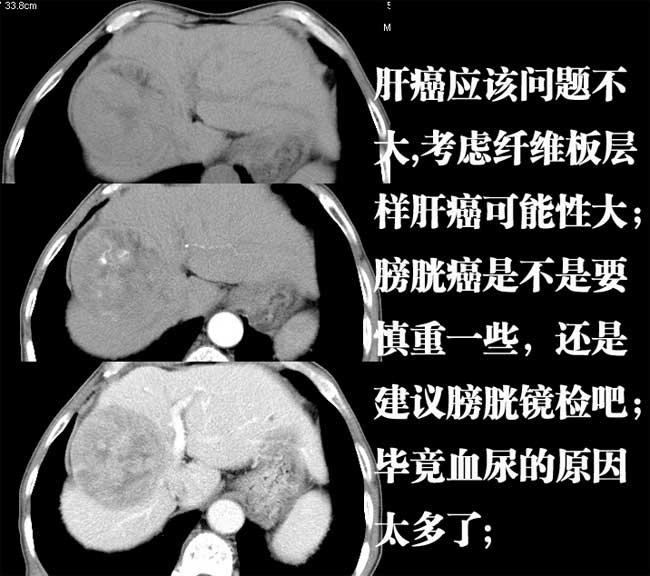

肝脏病变:

支持肝癌,以纤维板层型肝癌可能性大,膀胱癌。

肝脏内病灶有假包膜,增强扫描动脉期有动静脉瘘,有快进快出特点,考虑原发性肝癌。病灶内有裂隙样低密度影,以纤维板层样细胞癌可能性大。膀胱左侧乳头状占位,增强呈明显强化,左侧盆腔内有肿大淋巴结,结合有血尿病史,考虑膀胱癌左侧盆腔淋巴结转移。